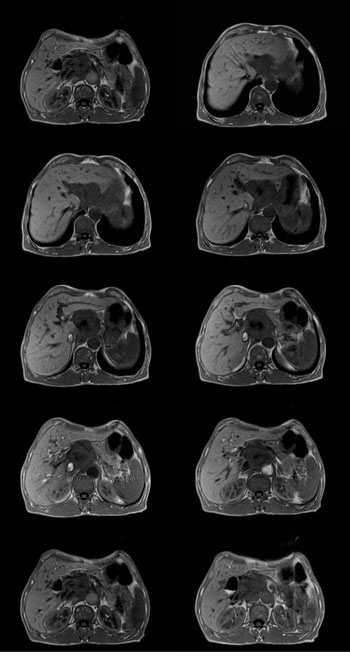

男:62岁:右上腹痛1月。b超报告肝左叶外侧段占位。请讨论灶来源!谢谢!!

腹主动脉前肝左叶后方占位,局部与肝脂肪间隙尚存,故排除左肝来源病变.病灶主体层面位置较高,胰腺受压前移.腹腔干明显拉长包埋.增强后肿瘤边缘性强化.胃小弯侧血管明显增粗.

考虑;后腹膜来源肿瘤.神经源性肿瘤>间叶源性肿瘤>淋巴源性肿瘤.